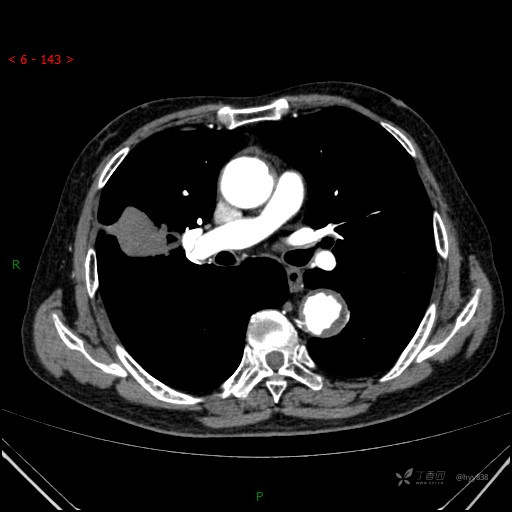

增强动脉期